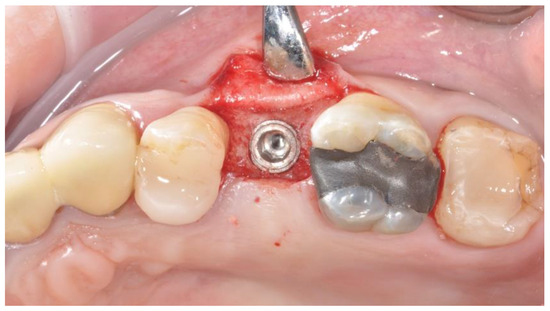

2.2. Surgical Procedures

2.3. Prosthetic Protocol